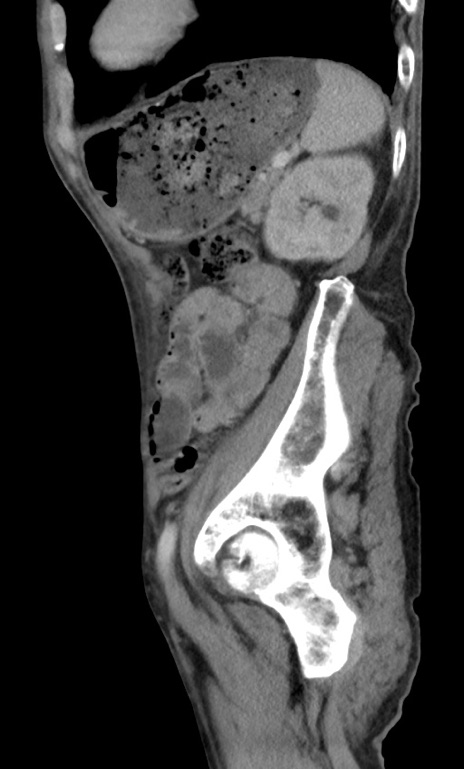

症例3(矢状断像)

冠状断像